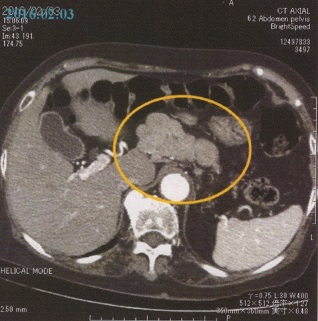

3月26日(土) 高瀬医師より、定例の検査報告である。

「先ず、腹部リンパ節の状態は先月より更に小さくなっているのが見て取れます。このような経緯から推察すると、やはり、腺がんと(奈良井病院で)言われた当初の診断そのものが疑わしく思われるほど落ち着いています。

(つまりは誤診であったのやも……というほどのニュアンスであったが、母の死後、再度、沢田医師を訪ねたところ、「定的脳手術などの然るべき検査に基づくものではないが、染色結果からは腺がんに見られるべき形が認められ、それは99%黒であった……」との見解を得た。つまり、不思議であろうと奇跡であろうとも、とにかく母はがんに勝ったのだ……)。

それに対し、脳腫瘍の長径は6㎝その周辺に浮腫みも出てきており、脳梁(のうりょう)体側部への広がりも認められます。

但し、脳動脈の閉塞は見られません。今後起こりうる病態としては、広範囲脳梗塞や腫瘍からの出血などが懸念され、それが一旦起きれば、急激な意識障害・呼吸および心停止につながる恐れもあります。ですから、向後(こうご)のリハビリ実施や息子さんがやるマッサージについては、特に細心の注意が要されますので気をつけてください」

言語・運動能力の衰えや食欲減退も、つまりは脳腫瘍の肥大によるもの。諸事、先が思いやられる……。(つづく)